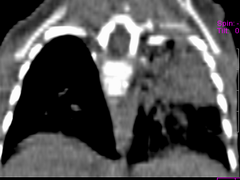

患儿 六月 咳嗽,反复发热二周,加重伴气喘3天

左肺呈大片状实变影,密度欠均匀,边界模糊,残存正常的肺组织呈气肿表现,右肺内可见磨玻璃样改变,如此年幼的婴儿首先考虑左肺发育不良并继发感染可能性大

此患儿于前日死亡,病检结果:

左肺发育不良伴感染.